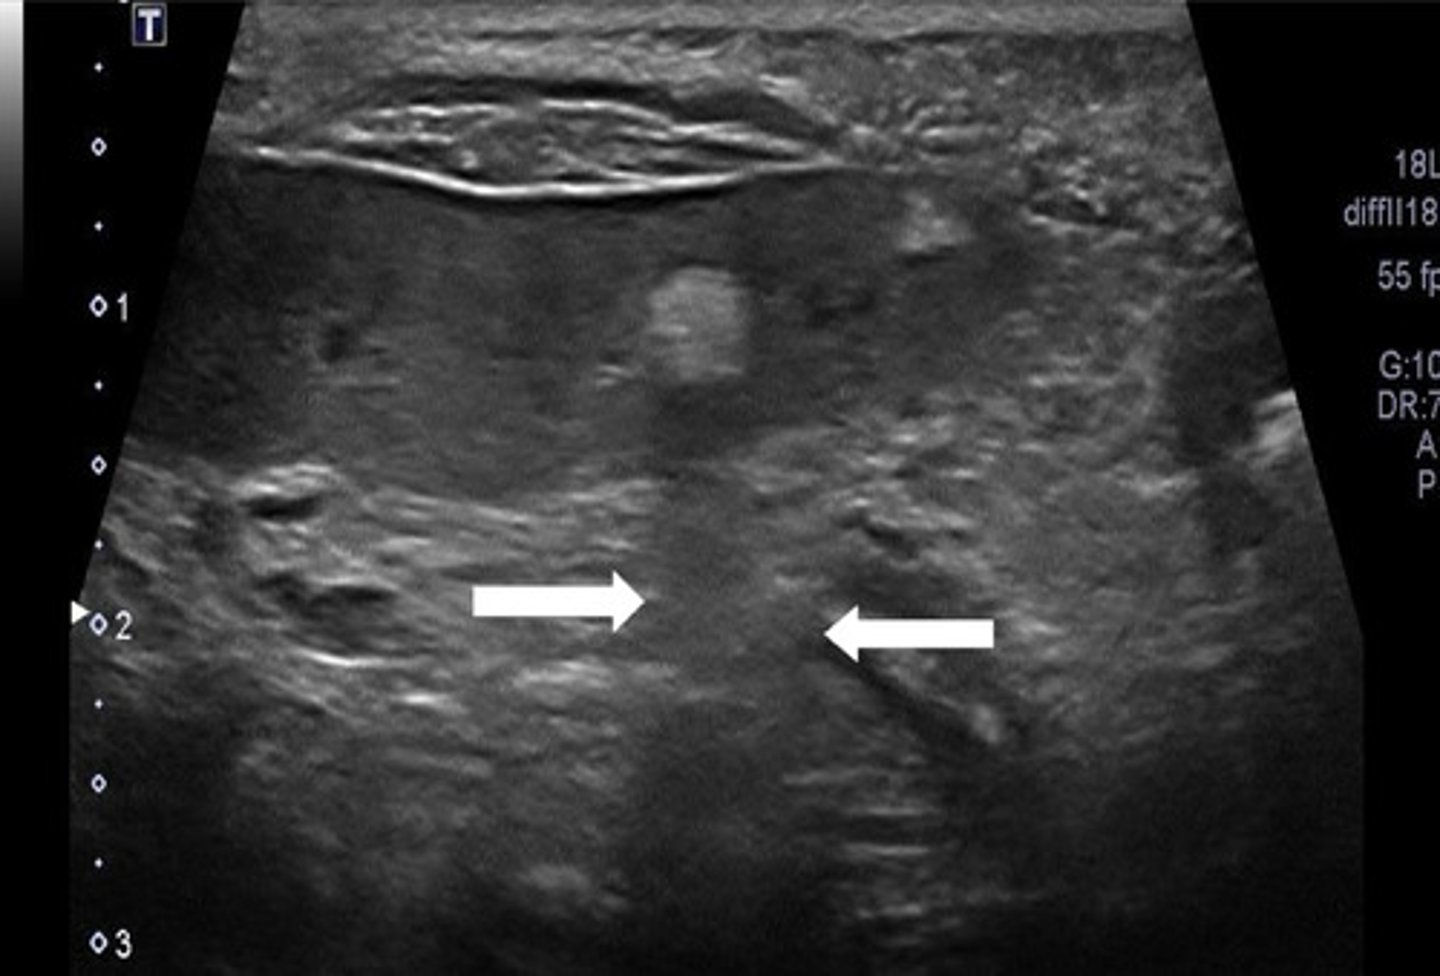

focal

are these ultrasound images of the spleen focal or diffuse?